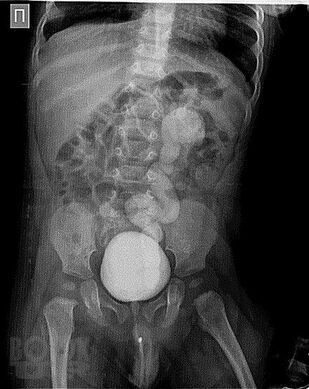

Учебное пособие предназначено для самоконтроля знаний студентов медицинских вузов, ординаторов и врачей детских хирургов, травматологов-ортопедов, детских урологов-андрологов и базируется на основных учебниках, европейских и российских клинических рекомендациях и учебных пособиях по детской хирургии. Используя его, можно в полной мере оценить усвоение студентами всего учебного материала и современных аспектов детской хирургии. Пособие содержит ситуационные задачи и ответы к ним, затрагивает все темы блоков модулей «Детская хирургия» и «Хирургические болезни у детей».